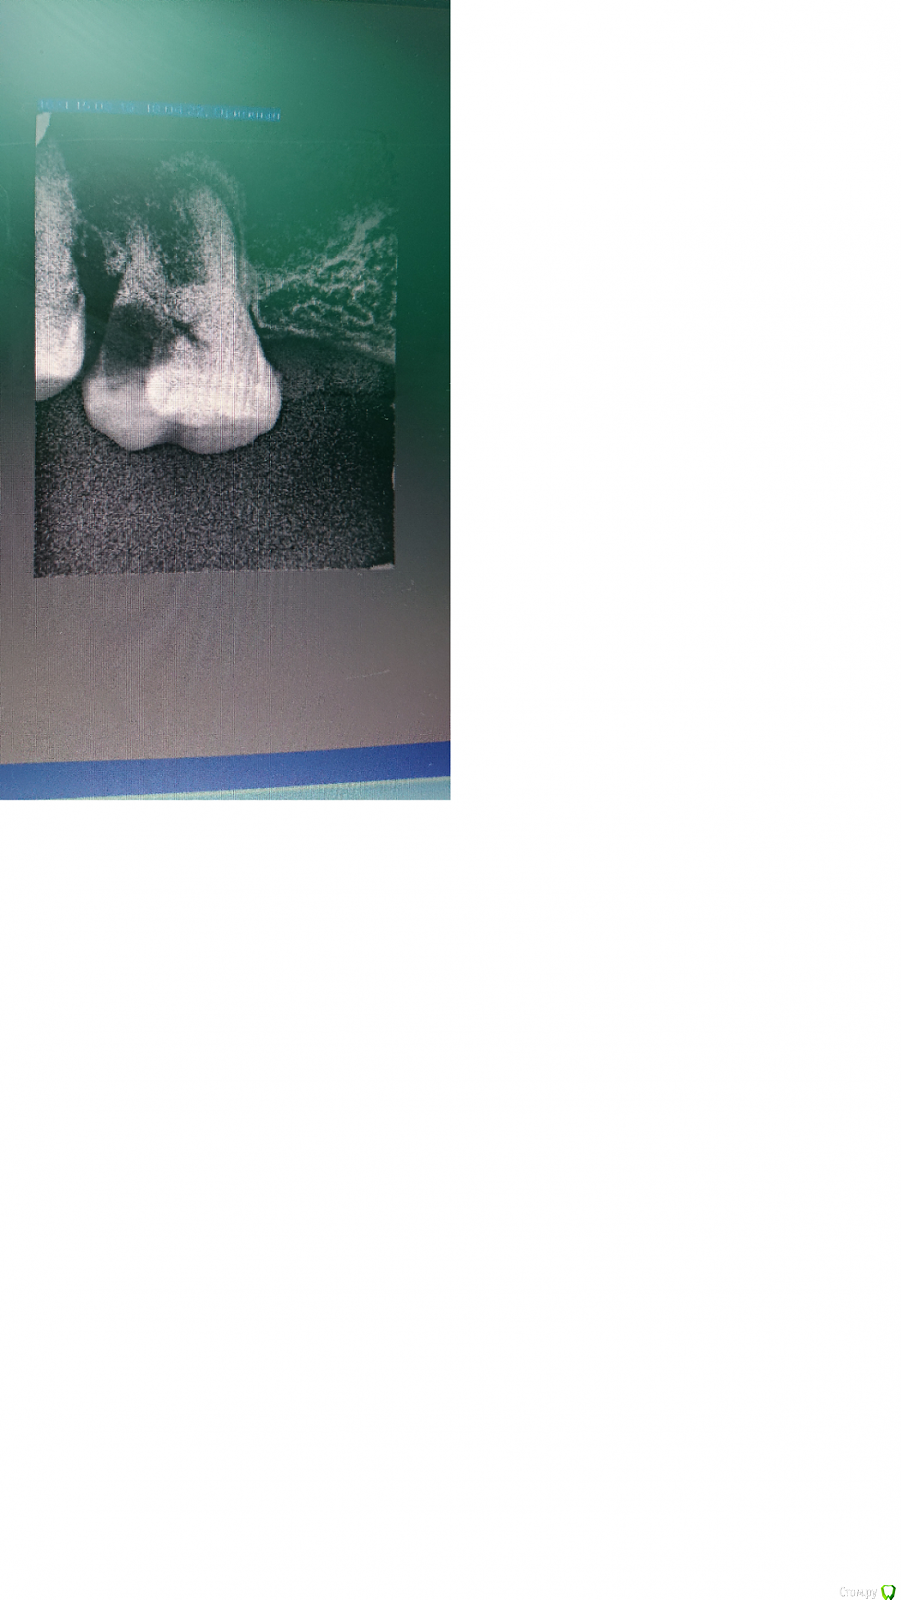

Прошу помочь советом. Зуб - верхняя шестерка.

Целесообразно ли лечение, есть ли  шансы на успех? Если да, какую тактику бы Вы выбрали? Можно ли спрогнозировать, насколько долго такой зуб протянет в случае лечения?

Либо не мучаться и сразу удалять?

1. Удаление поражённых тканей зуба, оценка оставшихся стенок. На этом этапе будет примерно понятен прогноз и его скажет только врач, которые будет лечить.

2. Хирургическое удлинение зуба в области подесневого разрушения.

3. Эндо лечение каналов и восстановление зуба под протезирование

4. Протезирование постоянной коронкой.